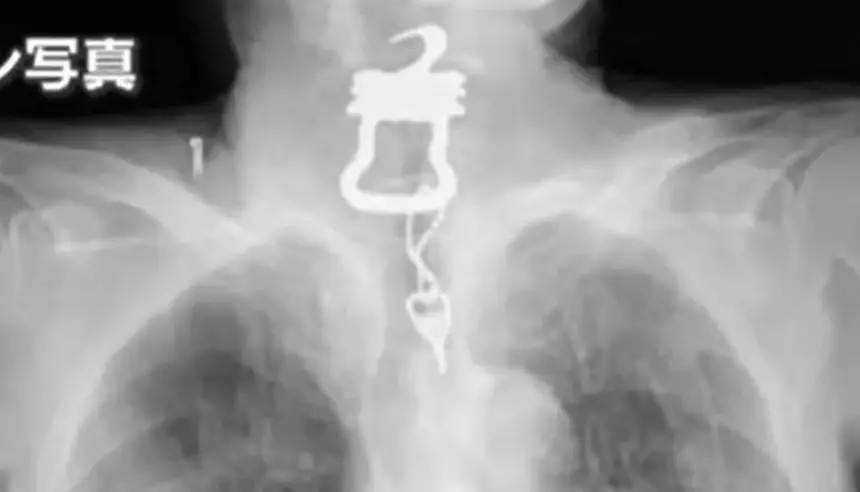

وتعود تفاصيل القصة إلى دخول "كينيتشي أونيشي"، البالغ من العمر 82 عاماً، المستشفى إثر إصابته بكسر في الصدر، لكنه توفي بعد أشهر، عقب ابتلاعه مفتاحاً طوله 12 سنتيمتراً، كان جزءاً من بدلة خاصة تُستخدم مع مرضى الخرف. ورغم إزالة المفتاح في وقت لاحق، إلا أن حالته الصحية تدهورت بسرعة، وانتهت بوفاته التي عُزيت رسمياً إلى مضاعفات كوفيد-19، في حين تؤكد أسرته أن السبب المباشر هو الالتهاب الرئوي الناتج عن الحادث.